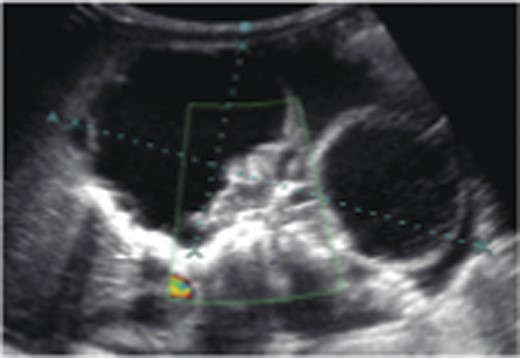

The case was referred to the Pediatric Surgery team postnatally. Birthweight was 3.6 kg. Apart from a distended abdomen, the child appeared grossly normal. Abdominal radiograph showed curvilinear calcifications over the right abdomen (Fig. 1). Ultrasonography (USG) revealed the presence of an echogenic line resembling long bones, giving rise to a provisional diagnosis of FIF (Fig. 2). An alpha feto protein (αfp) level taken at birth was markedly elevated at 13 200 IU/ml. Normal range of αfp at our center is taken to be 0–5.8 IU/ml at birth.